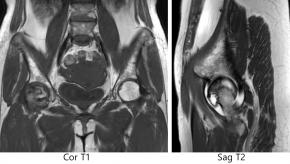

[Musculoskeletal [MS]] 46 Years/F, Rt hip pain

Questions What is the most likely diagnosis?

Answer Osteonecrosis of femoral head

Comments Ultrasound (US) is not the primary imaging modality for diagnosing femoral head osteonecrosis (avascular necrosis, AVN), but it can play a supportive or screening role in certain situations, particularly when MRI is not available or contraindicated.